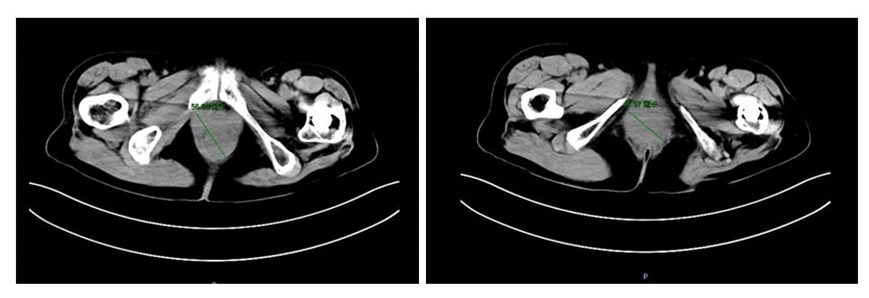

✦影像检查:

盆腔CT:子宫颈增大伴异常强化灶,符合宫颈癌表现;(因有节育器,未做盆腔MRI)。